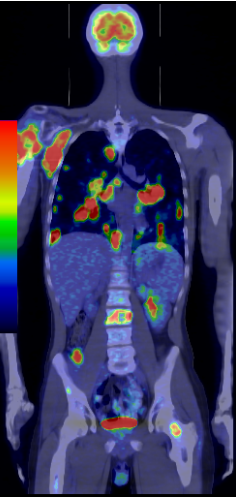

The most common clinical use of FDG-PET is in the form of whole-body scan, with oncologic indications. The majority of malignant tumors operate with higher energy consumption and show an increased glucose metabolism, consequently an increased uptake of FDG. The grade of malignancy is usually proportional to the rate of uptake. This method is useful in oncologic diagnostics, since it is capable to differentiate benign lesions from malignant ones. Whole-body PET imaging is capable to detect the primary tumor with local nodal metastases as well as distant metastatic lesions (staging) in one examination. (Figure 10.)

Test iframe

a

Image

b

c

d

10. Ewing’s sarcoma in the right humerus. Staging FDG PET-CT. PET Maximum Intensity Projection (MIP) image (a), transversal (b,c) and coronal (d) plane fused PET-CT images. Multiplex metastatic process with nodal, lung and bone involvement.